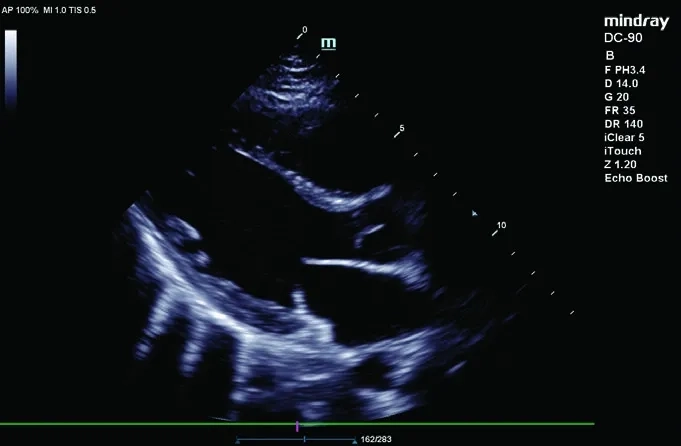

• Echo Boost — улучшенная визуализация структур сердца;

• AutoEF — ПО для автоматизированного расчета фракции выброса левого желудочка;